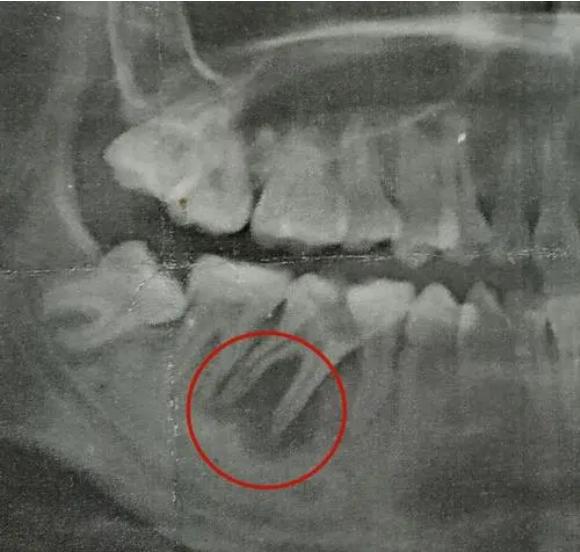

很多人不清楚牙齿根尖炎有什么症状,其实牙齿根尖炎不仅会出现牙齿伸长的现象,还会伴随叩齿疼痛、患病牙齿出现根尖周脓肿,部分人群会出现面部变形、畏寒发热等症状。

一般情况下,患有根尖炎症都是需要进行根管治疗,清除根管神经等受到感染发炎的组织,同时对根尖进行填充,隔绝空气,预防二次感染。

定期的口腔检查有助于提前知晓牙齿的情况,尤其是根尖炎,初期一般无法发现病症,在拍片检查的时候是能够较好地知悉口腔情况。